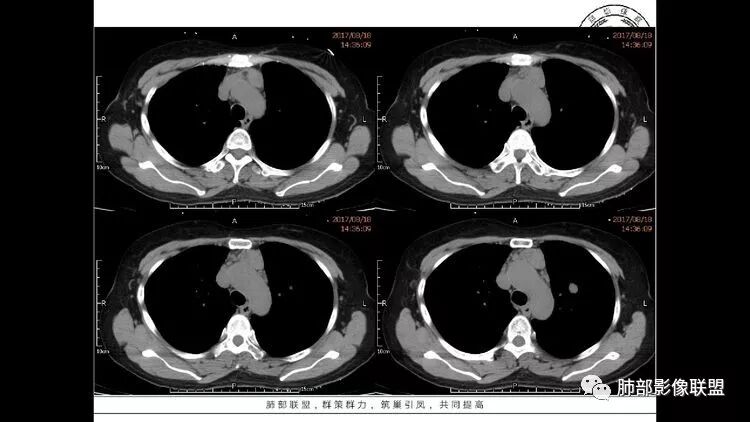

55岁女性,右眼红痛视力下降1天。既往有类风湿病史。两肺多发大小不等囊及结节,左下肺磨玻璃结节样病灶,纵隔占位。一元解释不了这么多不同病灶,二元甚至三元。纵隔恶性肿瘤并肺内转移?左下肺腺癌并肺内纵隔淋巴结转移?LIP?

多发气囊,气囊内可见血管进入,因患者眼干伴类风湿,可能有干燥综合征,那LIP可能性大。因为不是育龄期发病,可排除LAM。患者左纵膈淋巴结肿大,且有融合趋势,结合左下肺病灶,考虑合并恶性肿瘤,淋巴瘤?鉴别结节病

左肺下叶混杂密度病灶,其内可见空泡,周围ggo清楚,考虑浸润性腺癌。双肺散在多发薄壁囊腔和实性结节,以胸膜下及血管旁分布位于,气囊可见血管贴边征,双肺小叶间隔及中央间质增厚,局部可见磨玻璃影及树芽征,纵隔内淋巴结肿大,考虑LIP

综上,考虑左下肺浸润性腺癌+LIP

双肺多发大小不等囊腔,可见薄壁,部分囊腔内可见血管影,伴双肺多发结节,结合患者眼病及类风湿病史,考虑LIP可能大。另左肺下叶磨玻璃结节,边界清晰,内可见空泡,伴纵膈多发肿大淋巴结,不除外浸润性腺癌可能。

双肺多发散在斑片状磨玻璃密度影及大小不等的薄壁含气囊腔,下肺相对较多较大。双肺多发结节,界清,边缘光滑,分叶不明显。右肺下叶前外基底段散在斑片树芽。前上纵膈偏左侧不规则软组织团块,密度不均,其内可见不规则纤维样低密度,周围簇状小淋巴结。考虑1淋巴细胞间质性肺炎。2考虑纵膈胸腺淋巴瘤。